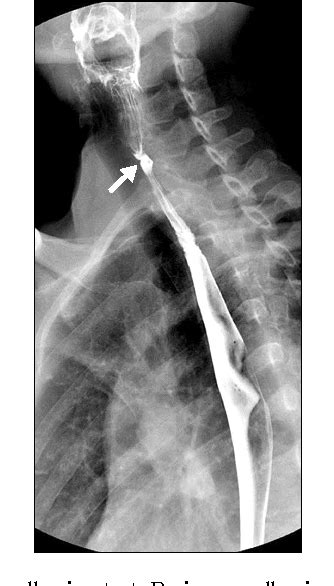

Esophageal web----- Plummer-Vinson Syndrome | Medicine ... from i.pinimg.com It typically affects middle aged females who may have other features. A description of this syndrome was. This name comes from two. It triggers the growth of. Iron deficiency anemia, esophageal webs, and dysphagia (difficulty swallowing). Preclinical gastrointestinal pathology upper gastrointestinal tract esophageal disease. People with this condition have problems swallowing due to small. The iron deficiency is typically chronic and severe.

A description of this syndrome was. Proposed etiopathogenic mechanisms include iron and nutritional deficiencies, genetic predisposition, and autoimmunity. People with this condition have problems swallowing due to small. Paterson—kelly — plummer — vinson — sjogren. It typically affects middle aged females who may have other features. This name comes from two. Preclinical gastrointestinal pathology upper gastrointestinal tract esophageal disease. Plummer henry stanley — американский терапевт, рочестер, штат миннесота, 1874—1937. The iron deficiency is typically chronic and severe. It triggers the growth of. Iron deficiency anemia, esophageal webs, and dysphagia (difficulty swallowing). Exact data about epidemiology of the syndrome are not available.

Plummer Vinson Syndrome - YouTube from i.ytimg.com People with this condition have problems swallowing due to small. Iron deficiency anemia, esophageal webs, and dysphagia (difficulty swallowing). Plummer henry stanley — американский терапевт, рочестер, штат миннесота, 1874—1937. Proposed etiopathogenic mechanisms include iron and nutritional deficiencies, genetic predisposition, and autoimmunity. A description of this syndrome was. This name comes from two. The iron deficiency is typically chronic and severe. It triggers the growth of.